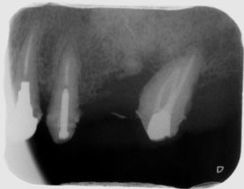

左上6番の近心に骨欠損があるため再生療法を行い、骨を回復した症例

歯周病治療前と治療後の比較